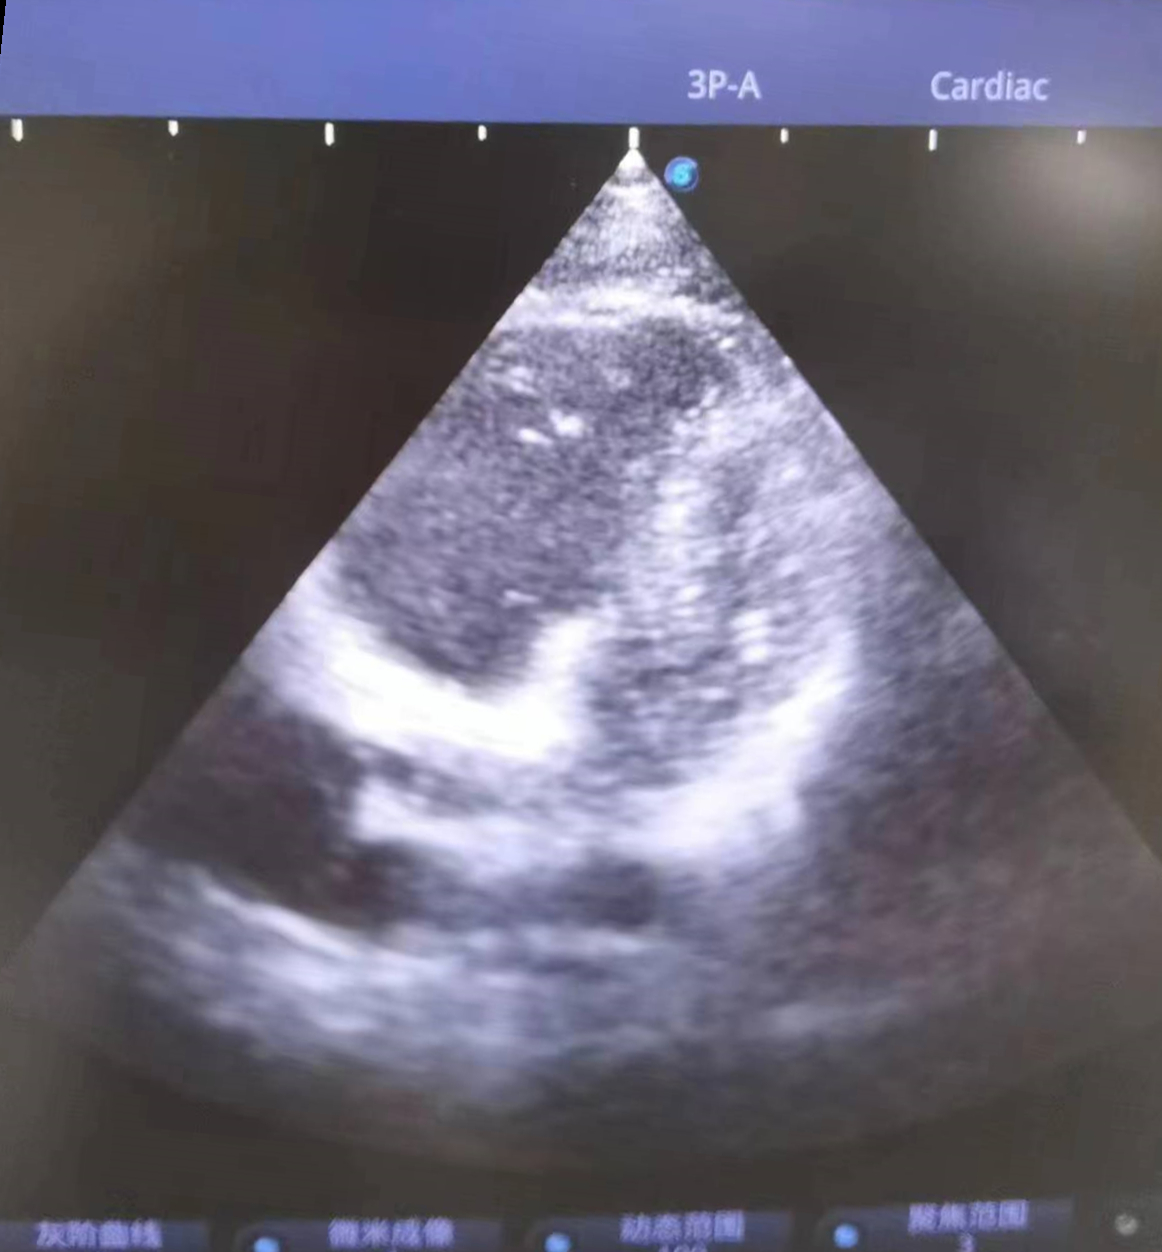

当天9点25分,小杨被送至急诊科,此时他面色苍白、呼吸困难、烦躁不安,无法配合治疗。急诊科医护紧急给予对症治疗,同时联系重症医学科(ICU)、心血管内科、超声影像科专家会诊。9点35分,小杨突然丧失意识,双侧瞳孔散大、心跳呼吸暂停,急诊科联合ICU医生立即行胸外心脏按压,呼吸球囊辅助呼吸,气管插管等抢救措施,因病情尚未明确,ICU医师紧急联系超声科医生行床旁心脏超声,心脏各切面均可见右心急性扩张,胸骨旁短轴切面可见左心室明显“D字征”,根据病人临床表现及超声检查,高度可疑为“急性大面积肺栓塞”,追问患者朋友,进一步了解到患者近日有下肢疼痛感,且既往有下肢骨折史,进而超声发现患者右下肢多处血栓形成。明确诊断后,阳逻院区院长、心血管内科学科带头人杨波当机立断给予阿替普酶治疗,为患者紧急溶栓。持续近一个小时的心肺复苏和溶栓治疗将小杨从死神手里拉了回来,10点14分,小杨心跳、呼吸恢复。

患者心脏彩超呈D字征,提示肺动脉高压,肺栓塞可能

患者彩超检查报告

综合考虑患者病情、病史和各项检查等情况,重症医学科肖志英主任带领科室团队制定针对性治疗方案,紧急给予50mg阿替普酶溶栓及肝素钠抗凝,结合脑保护、CRRT、抗休克、呼吸机辅助呼吸、床旁重症超声技术等多项高级生命支持。经历24小时生命大接力,3月2日上午,小杨呼吸循环稳定下来,意识恢复清醒,并成功拔除气管插管。